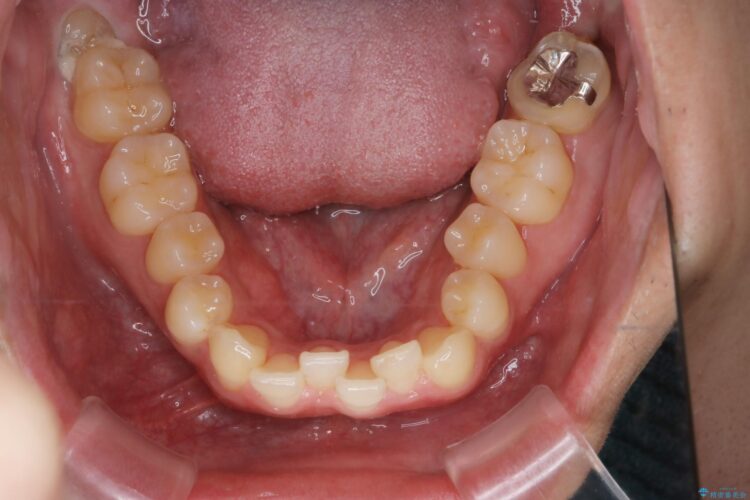

上の八重歯と下の歯のがたつきが気になるとご来院された患者様です。

精密検査の結果、抜歯の必要はないと判断しました。臼歯を遠心移動させ、歯列をワイヤーで整えることでスペースを確保し、IPR(歯と歯の間を削る処置)を加えて歯並びを綺麗にする治療計画を立てました。